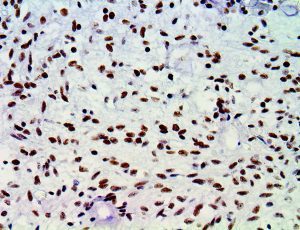

It is the ICU physician who is most likely to witness one of the deadliest manifestations of the abnormal immunological response, the cytokine storm syndrome (CSS). This response is also referred to by some as the cytokine release syndrome (CRS). CSS is characterized by continuous activation and expansion of macrophage and lymphocyte populations, which secrete large amounts of cytokines, causing the cytokine storm. This massive cytokine release is akin to hemophagocytic lymphohistiocytosis (HLH) disease, a syndrome characterized by initial unchecked and persistent activation of cytotoxic T lymphocytes and NK cells.

Clinical and laboratory manifestations of HLH include fever, enlarged liver and/or spleen, neurologic dysfunction, coagulopathy, liver dysfunction, cytopenias (i.e., low levels of erythrocytes, leukocytes, and/or platelets), hypertriglyceridemia, hyperferritinemia, hemophagocytosis, and eventually diminished NK cell activity as the immune system becomes progressively paralyzed. HLH can be familial (primary HLH) or secondary to another disease process (sHLH), such as rheumatic disease, in which it is referred to as macrophage activation syndrome (MAS, characterized by elevated ferritin).